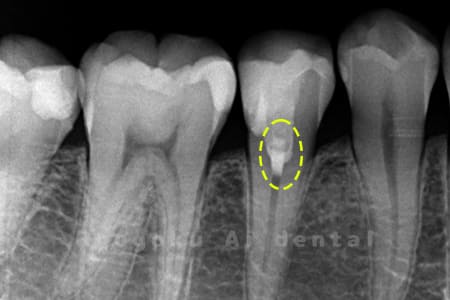

Case03

-

- 原因

- むし歯

- 治療期間

- 補綴装着期間を含めて3回

- 治療内容

- 断髄治療

- 治療費用

- 66,000円

違和感があるとのことでレントゲン撮影を行なったところ、プラスチックの被せ物の中で虫歯が広がっていると判断。レントゲンの状態からも神経にかなり近いため、患者様と相談し、断髄治療を行なったケースです。3年間のフォローアップ期間中で現在トラブルはなし。

<リスク・副作用>

術後は痛み、腫れ、痺れなどの副作用が生じる場合があります。症状が再発する可能性があります。その場合は抜髄する必要があります。